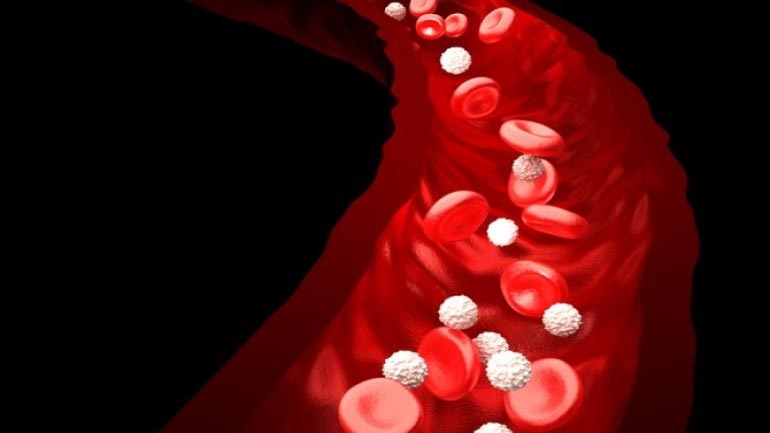

Κινήσου ενάντια στη θρόμβωση

Το μήνυμα «Κινήσου ενάντια στη θρόμβωση» ήταν το κεντρικό μήνυμα όλων των ομιλητών κατά τη διάρκεια Συνέντευξης Τύπου που οργάνωσε το Ι.Μ.Ε.Θ.Α., με αφορμή τον εορτασμό της Παγκόσμιας Ημέρας Θρόμβωσης (13 Οκτωβρίου). Ο εορτασμός της Παγκόσμιας Ημέρας Θρόμβωσης που φέτος κλείνει τα 10 χρόνια, έχει την επιστημονική αρωγή 19 Επιστημονικών Εταιρειών που σχετίζονται με τη […]